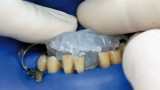

One of the more popular methods of stabilising loose teeth is to splint them. This method, aiding other methods of treatment, is generally used. One of the most modern materials used in dentistry for splinting teeth, is polyamide tape. In the case described the authors show how to simplify the whole procedure and limit the risk of making a mistake, particularly in the situation of total loss of one tooth. This was achieved thanks to the use of an index made out of transparent silicone.

Jedną z popularniejszych metod stabilizacji zębów rozchwianych jest ich szynowanie. Metoda ta, wspierająca inne metody leczenia, jest powszechnie stosowana. Jednym z najnowocześniejszych materiałów wykorzystywanych w stomatologii do szynowania zębów jest taśma poliaramidowa. W opisanym przypadku autorzy pracy przedstawiają sposób uproszczenia całej procedury i ograniczenia ryzyka popełnienia błędu, szczególnie w sytuacji całkowitej utraty zęba. Uzyskano to dzięki zastosowaniu indeksu wykonanego z przezroczystego silikonu.